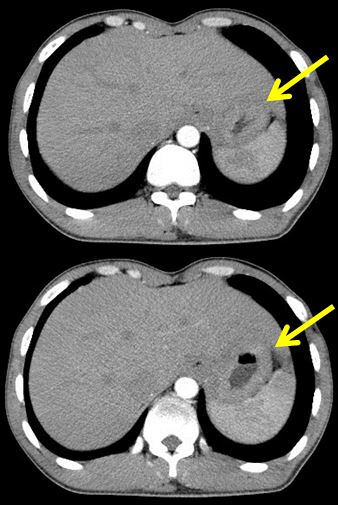

Trước hóa trị

Khối u thâm nhiễm tổ chức xung quanh | Sau 6 đợt hóa trị

Thành dạ dày bờ không đều, không còn thâm nhiễm tổ chức xung quanh |

Hình 4: Kết quả chụp CT bụng trước và sau 6 đợt hóa trị.